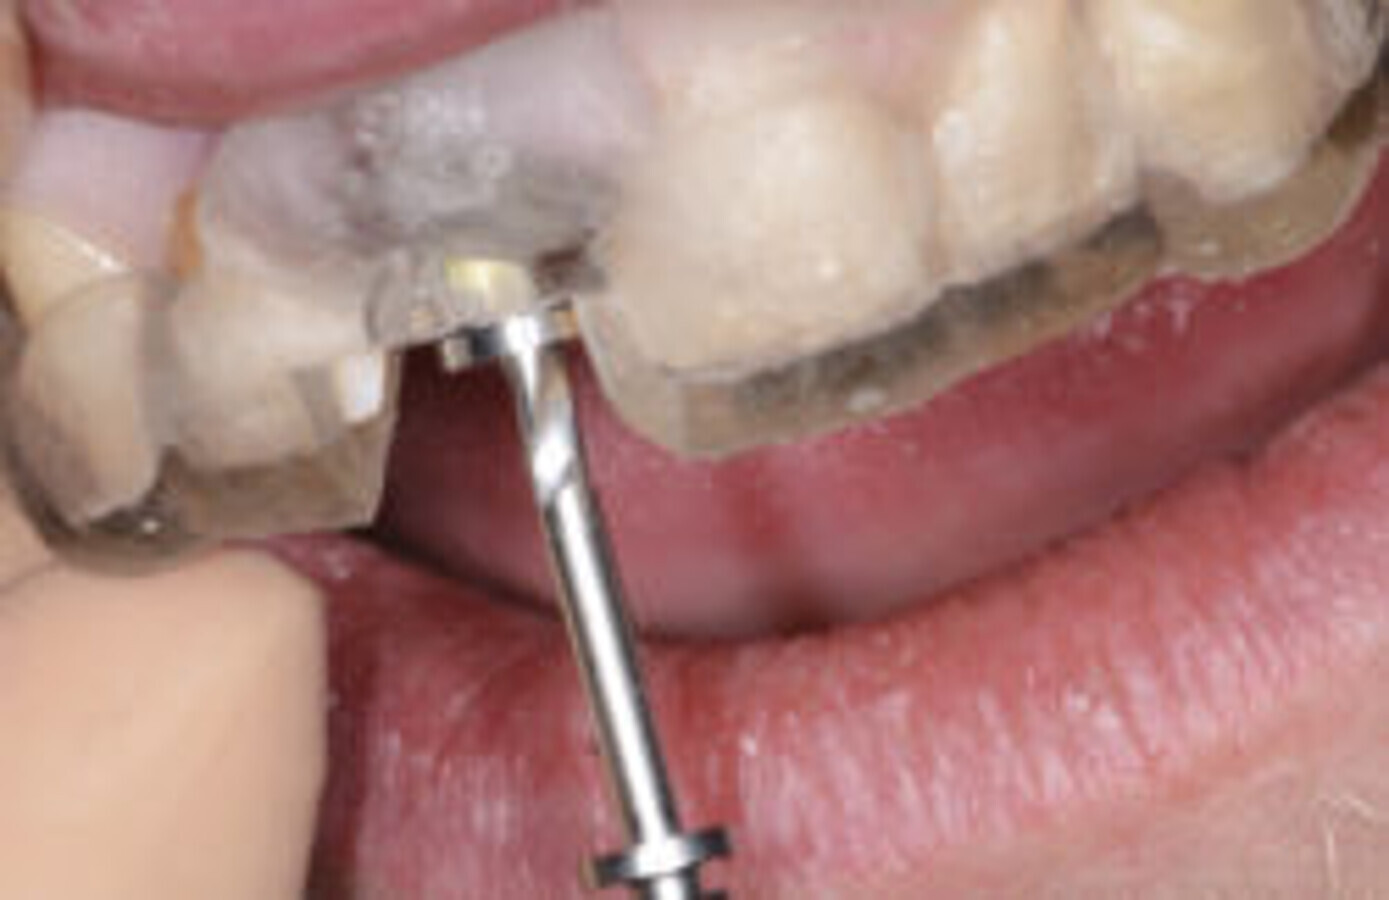

本文将逐步展示一单颗义齿美学修复案例。患者由于#11牙折前来就诊(图1)锥形束计算机断层扫描(CBCT)证实了牙折,并显示唇侧牙根有外部吸收(图2)。患牙必须拔掉,并决定在立即种植后进行临时的美学种植修复。计划采用短期的非包容式装载方式进行即刻种植体植入。

图1. 治疗前情况,考虑拔牙#11。